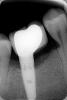

Dagaeva Опубликовано 5 июня, 2012 Автор Поделиться Опубликовано 5 июня, 2012 хотелось бы конечно увидеть снимок, но судя по вашему описанию вариант только один - удаление имплантата.Добрый день. Снимки прикрепила. Посмотрите , пжлст. спасибо Ссылка на комментарий

kriokov Опубликовано 5 июня, 2012 Поделиться Опубликовано 5 июня, 2012 Ваше слово, как самый страшный приговор( я очень этого боюсь. А что Вы увидели на этом снимке, что так безкомпромисно "удаляйте". Мне нужно понимать , т.к. моя клиника и врачи в ней против...говорят можно спасти. Что у меня там - инфекция, аллергия, травма...????Заранее спасибо.мнение, не истина в последней инстанции. На снимке видно убыль кости с оголением третьего витка резьбы имплантата с одной из его поверхностей. Дождитесь ответа других врачей форума, обсудите проблему в клинике, примите решение. Ссылка на комментарий

Dr. Surkin Опубликовано 6 июня, 2012 Поделиться Опубликовано 6 июня, 2012 нужно видеть состояние в полости рта, есть возможность сделать качественные фото??. Может и есть шансы сохранить, но никакой эстетики не будет. +1 Оголена и инфицирована шероховатая часть имплантата. Никаким образом изгнать инфекцию и наростить сверху кость невозможно. Единственный вариант сохранения имплантата, это раскрыть его полностью от десны (откинуть лоскуты), удалить грануляции - воспалительные мягкие ткани - вокруг имплантата, затем стоматологическим бором "спилить" шероховатую поверхность имплантата, заполировать её до блеска до уровня кости. Дать зажить примерно месяц. Десна опустится и станет видно соединение имплантат-формирователь десны. Установить постоянный абатмент. Обточить его вровень с шейкой имплантата и снять слепок, как если бы это был естественный обточенный зуб. Изготовить новую постоянную коронку. Ссылка на комментарий